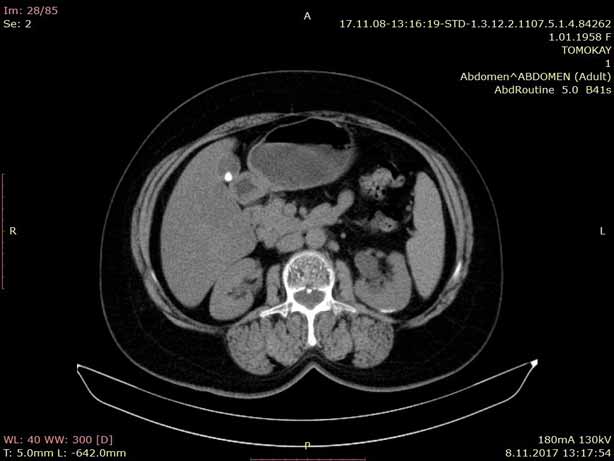

Bilgisayarlı Tomografi (BT) ileri bir X ışını teknolojisidir. BT vücudun istenilen bölgesinden kesit kesit (dilim şeklinde) görüntü alınmasına olanak verir. Bu gelişmiş resimler dönen odaklanmış bir X ışını üreticisinin hastanın etrafında dönmesiyle oluşturulur. Vücudun farklı bölgeleri ve organları incelenir.

BT cihazının masasına yatmanız istenecektir. Bu masa yuvarlak bir boşluğun içine doğru ilerleyecektir. Çekim başlayınca BT makinesinden bazı sesler duyacaksınız. Bu sesler sizi rahatsız etmesin; çünkü bu sesler X ışınları oluşurken ve sizin vücut bölgenizden kesit kesit görüntüler alınırken ortaya çıkan seslerdir. Her kesitte BT makinesi ayrı bir görüntü oluşturur. X ışınlarından alınan bilgiler son teknoloji bilgisayar sayesinde görüntü haline dönüştürülür. Görüntüler dijital ortamda tutulur, Workstation (İş istasyonu) sayesinde merkezimizdeki Radyologların bilgisayarlarına gönderilir. Film olarak veya CD ortamında hastaya verilir.

BT ile torakstaki (akciğer, mediastinum, kalp ve damarlar, göğüs duvarı) kitle lezyonu (tümörler), infeksiyon, inflamasyon gibi hastalıklar teşhis edilmektedir.